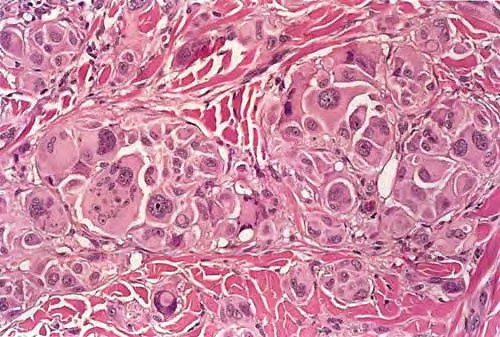

metastasis